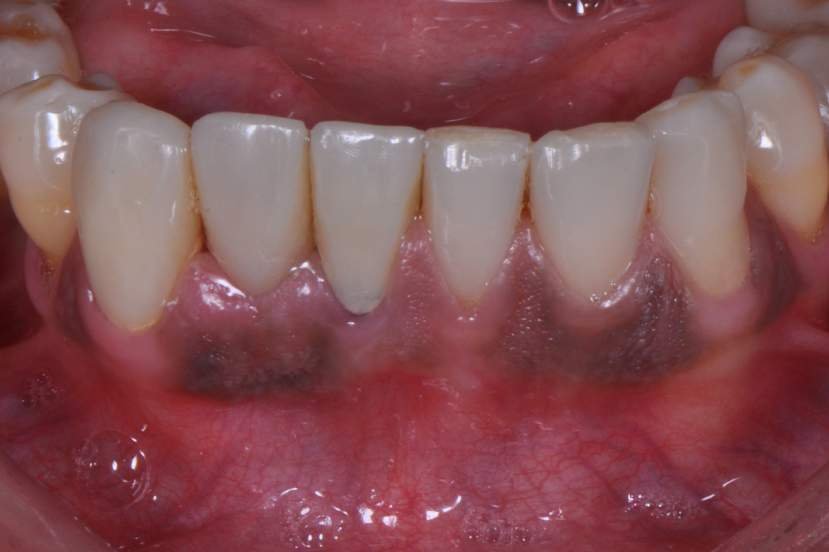

CASO CLÍNICO

Paciente com perda do incisivo central inferior do lado direito, utilizando uma prótese fixa em zircônia com estética e adaptação deficientes.